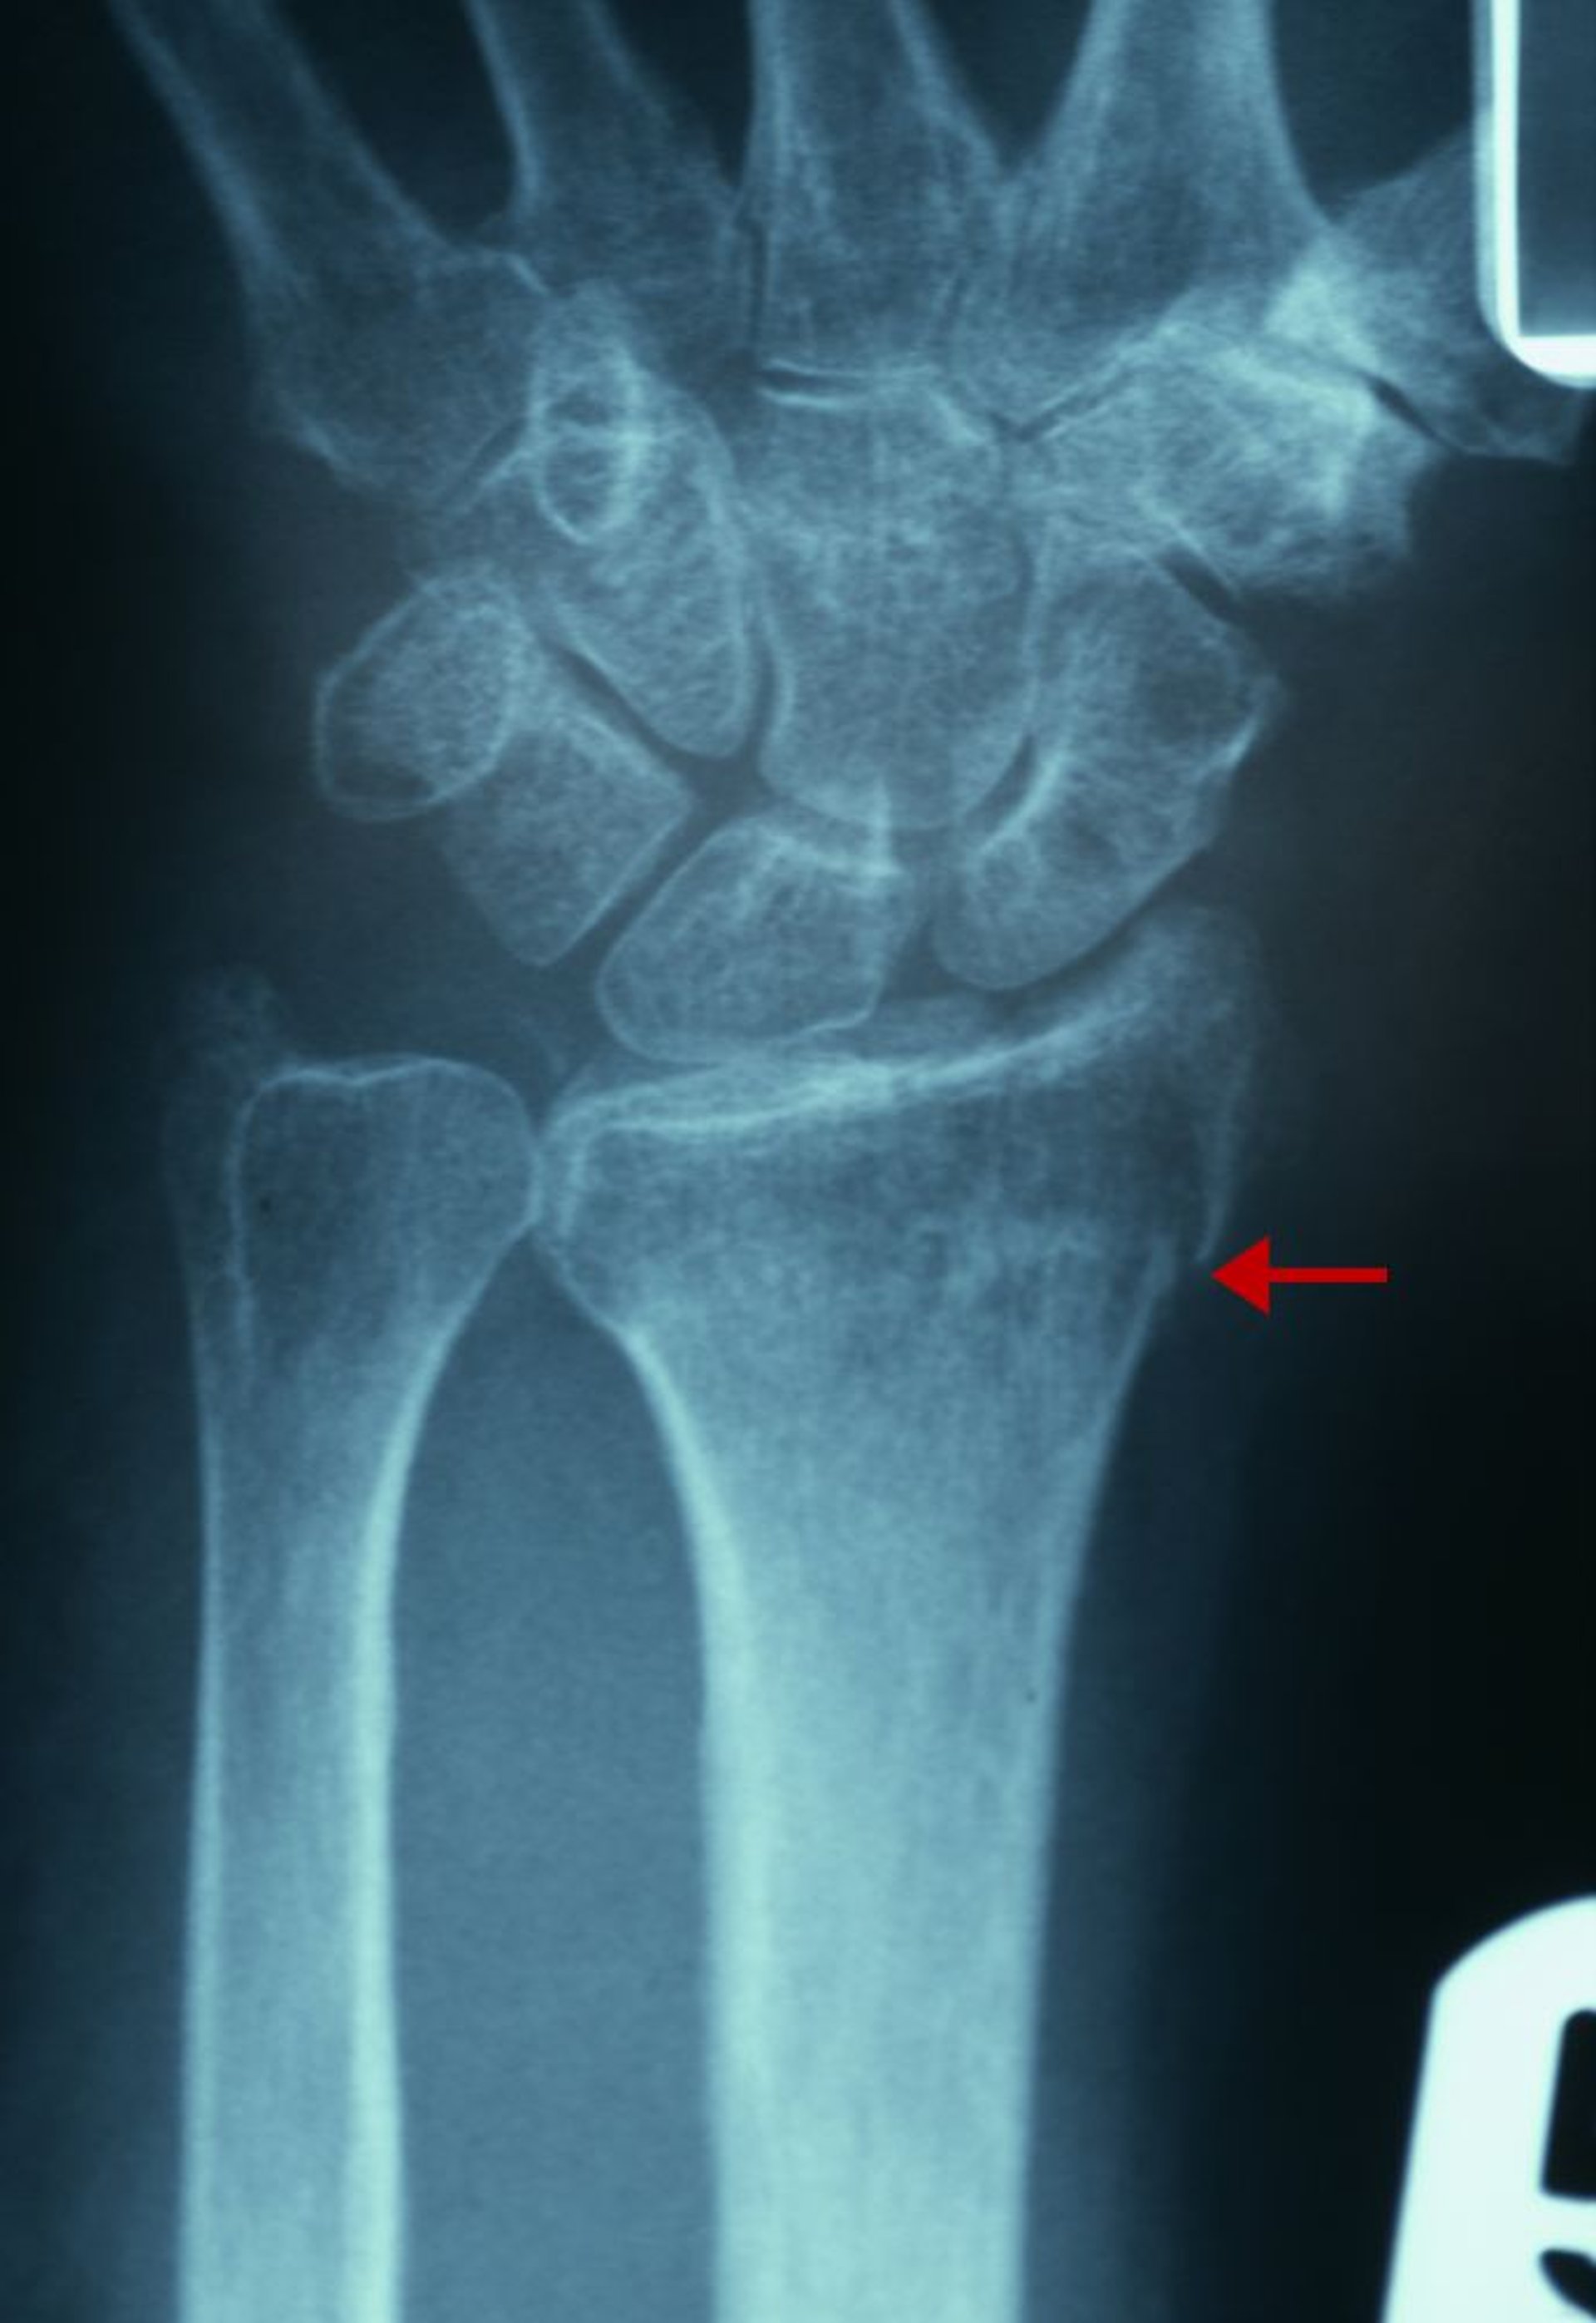

Fractura sutil del radio distal

La evidencia radiológica de esta fractura incluye una solución de continuidad en la corteza de la cara radial del radio distal (flecha) y un aumento de la densidad trabecular del radio distal.